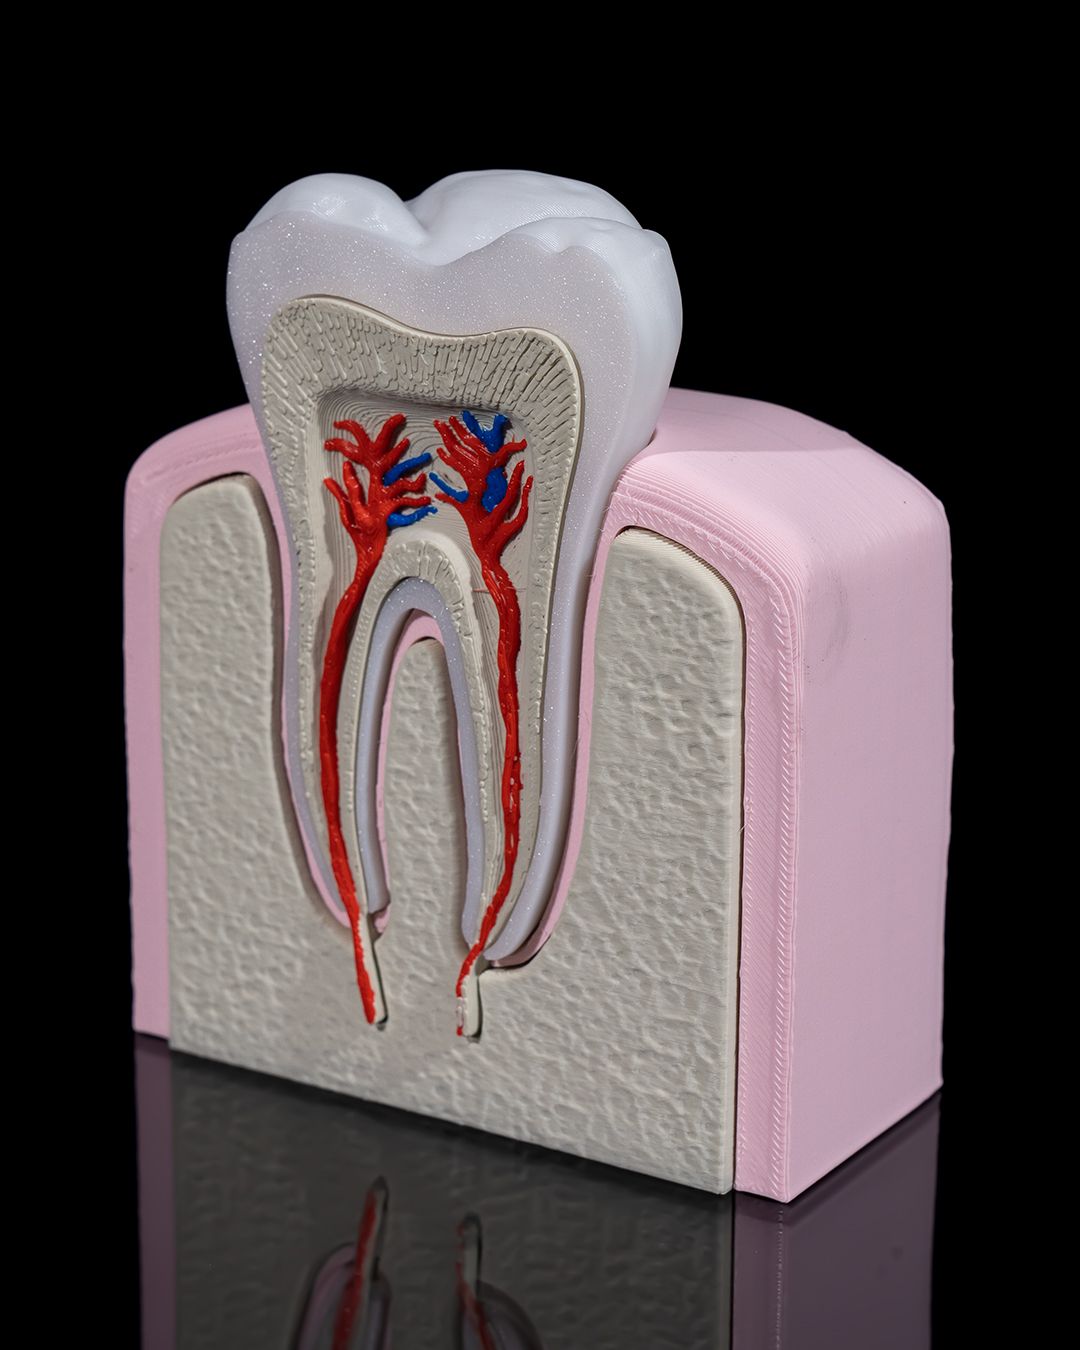

🦷 3D Printed Healthy Premolar Tooth – Precision You Can Smile About

Perfect for dental education, display, or interactive learning, this anatomically accurate premolar model showcases the structure and strength of a healthy adult tooth. It’s a striking blend of science and craftsmanship, ideal for classrooms, clinics, and curious minds.

- True-to-life size and shape for tactile exploration

- Clearly defined cusps, root formation, and enamel contours

- Excellent for explaining oral hygiene, dental anatomy, and procedures